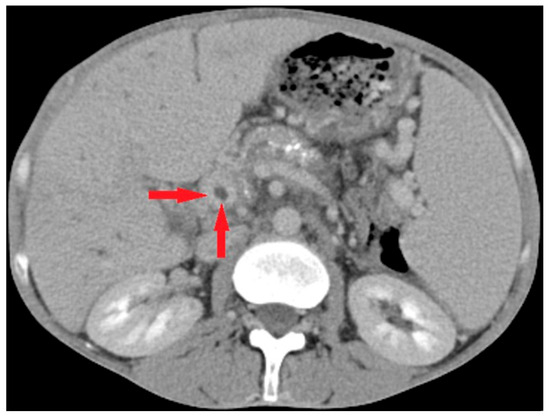

4.3.3. Imaging in Pylephlebitis